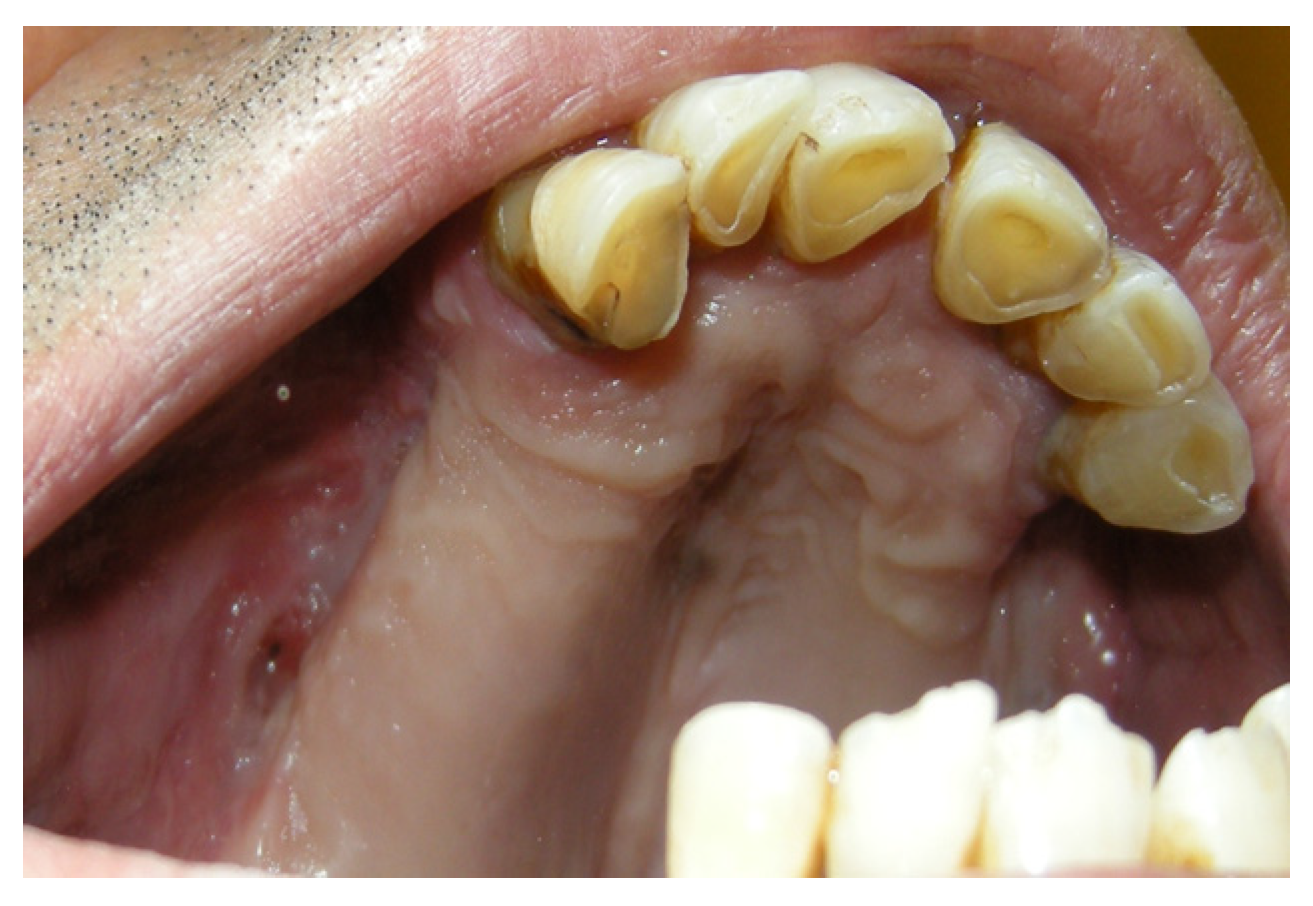

3.1.4. Case 4: P.M.A.

| P.M.A | X | * | 5 | 5 |